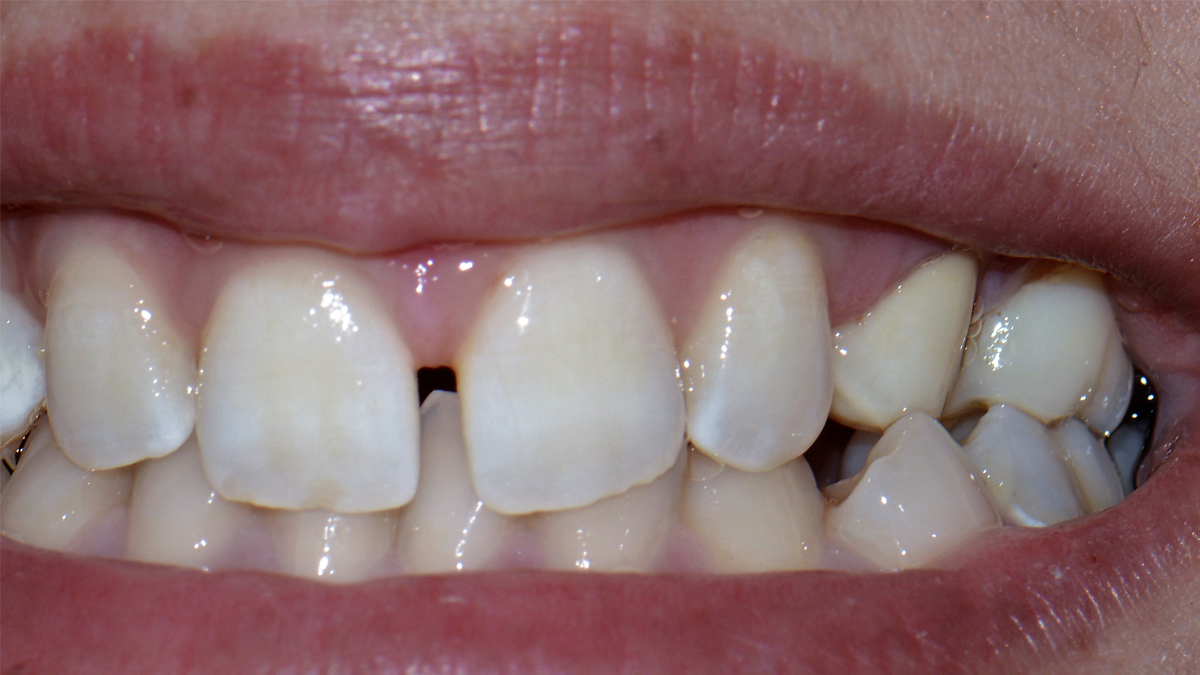

Fogaink külső felszínét szervezetünk legkeményebb anyaga, a zománc borítja. A zománc 98%-át szervetlen anyagok alkotják, amelyek savhatásra képesek kioldódni. Ez a magyarázata annak, hogy egy ilyen kemény anyag képes meggyengülni, sőt üreg képződhet pusztán baktériumok és szénhidrát hatására. Abban az esetben, ha a kórokozók átjutottak a zománc rétegen, a fogszuvasodás terjedése felgyorsulhat , ilyenkor általában már panaszos a fog, hidegre, édesre intenzívebben reagál.

A tömőanyag tulajdonságaiból adódóan ma már, ha az üreg nem túl nagy, minden fogcsoport tömésére alkalmazható. Rágófogakban képes helyreállítani a funkciót, azaz egy erős, a rágóerőkkel szemben ellenálló tömés készíthető, frontfogakba (metszőfogak) pedig készülhet olyan esztétikus, észrevehetetlen tömés, mely kedvezően befolyásolhatja megjelenésünket, arckarakterünket.